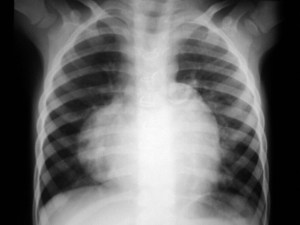

SIGNO DEL CASQUETE APICAL IZQUIERDO

La aparición de una densidad en el ápex pulmonar izquierdo, de borde inferior cóncavo y bien delimitado (casquete apical) en un paciente con traumatismo torácico, debe hacernos sospechar la existencia de una rotura aórtica.

Deben excluirse otras causas de casquete apical, especialmente las lesiones residuales tuberculosas, que suelen acompañarse de otros hallazgos como tractos fibrosos pleuro-parenquimatosos, pérdida de volumen en el lóbulo superior, granulomas, etc.

Mostramos un caso de rotura aórtica por accidente de moto. En este paciente también aparece el signo de la alteración del contorno aórtico.